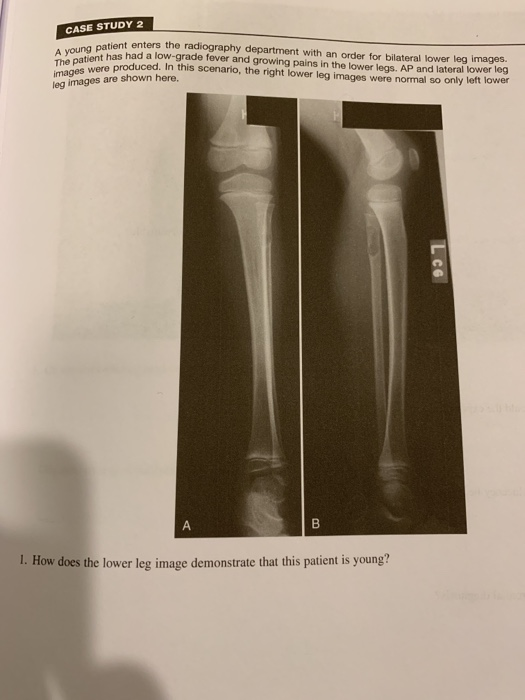

Solved Case Study 2 Patient Enters The Radiography Depart